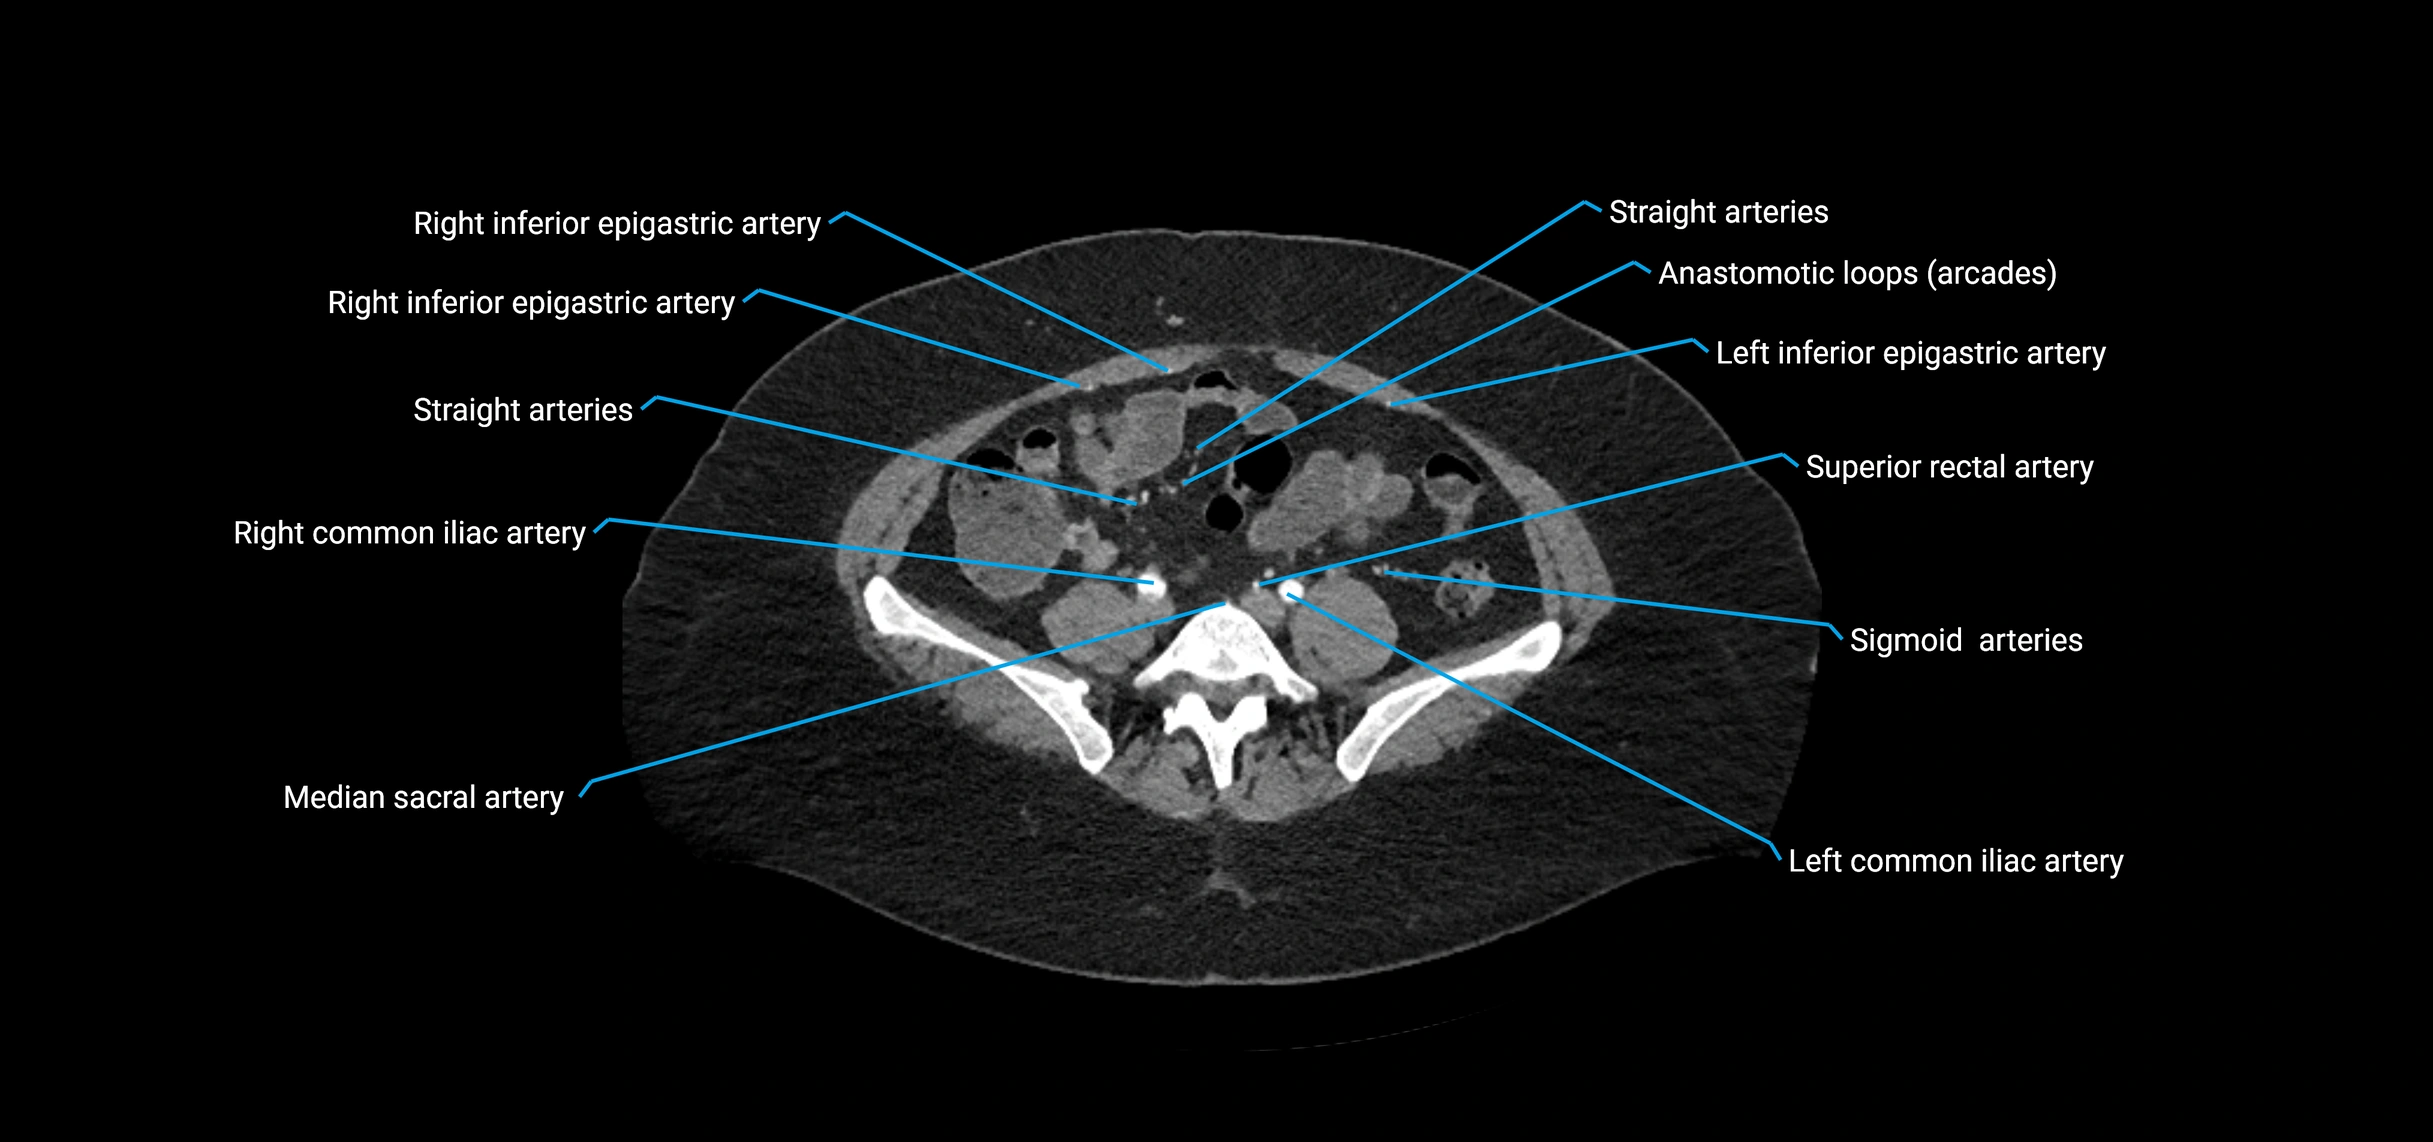

Contrast-enhanced CT (CTA):

• Gold standard for abdominal aortic imaging

• Provides excellent detail of lumen, wall, aneurysm, thrombus, and branch vessels

• Multiplanar and 3D reconstructions help in aneurysm measurement, stent graft planning, and dissection evaluation